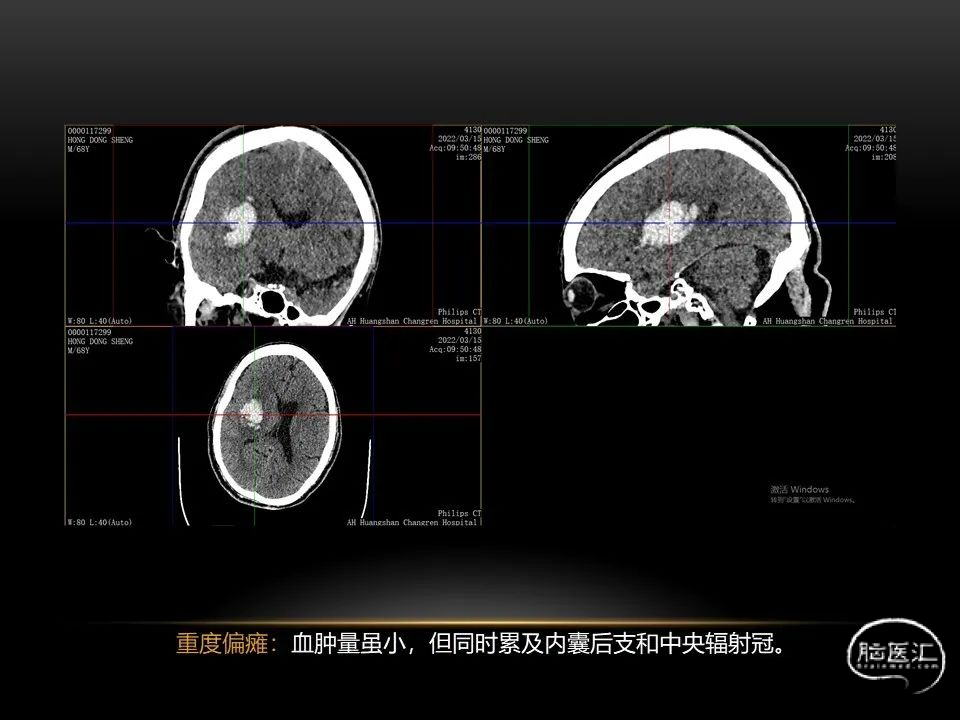

相近的脑出血量,

发生在不同部位有截然不同的症状,

同样也决定了预后也是截然不同的。

自发性脑出血临床上很常见,不同原因有特征性的出血部位。例如:基底节出血和丘脑出血大多是高血压性脑出血;脑叶出血,特别是多次复发的脑叶出血多见于老年人的脑血管淀粉样变。

自发性脑出血不仅仅累及内囊后肢才会出现偏瘫及偏身感觉障碍,病变累及大脑脚或辐射冠同样有可能有类似症状和体征。内囊、辐射冠、大脑脚等结构之间是延续的,只是不同区域不同名称而已。定位诊断需要对解剖结构概念清晰,读片准确辨认,灵活掌握。